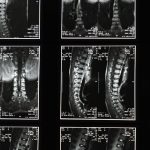

La sténose foraminale cervicale est une condition où les nerfs situés dans la colonne cervicale sont comprimés, causant des douleurs, des engourdissements et une faiblesse dans les bras et les mains. Cette pathologie peut être débilitante, mais il existe des traitements efficaces. La décompression neurovertébrale s’est révélée être une solution non invasive qui cible cette compression en créant un espace dans les foramen pour libérer les nerfs. Grâce à cette technique, les patients peuvent non seulement éprouver un soulagement significatif de la douleur, mais également une amélioration de la fonctionnalité et de la qualité de vie.

La sténose foraminale cervicale est une condition qui provoque des douleurs en raison de la compression des nerfs dans la région cervicale. Elle peut être causée par diverses affections telles que l’arthrose, les hernies discales ou le durcissement des ligaments. La décompression neurovertébrale émerge comme une solution efficace pour atténuer ces douleurs et améliorer la qualité de vie des patients touchés.

La sténose foraminale se produit lorsque les ouverts à travers lesquels les nerfs sortent de la colonne vertébrale se rétrécissent. Cela peut entraîner une compression des nerfs, causant des douleurs, des engourdissements ou une faiblesse dans les bras ou les mains. Les symptômes peuvent varier en fonction de la gravité de la compression.

La sténose foraminale cervicale est une condition courante qui peut entraîner des douleurs significatives et une limitation de la mobilité. Cette affection se produit lorsque les espaces à travers lesquels les nerfs rachidiens passent deviennent rétrécis, provoquant des compressions nerveuses. La décompression neurovertébrale s’avère être une option thérapeutique efficace pour soulager les symptômes liés à cette pathologie. Dans cet article, nous explorerons comment cette technique non invasive peut aider à soulager la douleur et à améliorer la qualité de vie des patients souffrant de sténose foraminale cervicale.

Comprendre la Sténose Foraminale Cervicale

La sténose foraminale cervicale survient lorsque les foramens, ou ouvertures latérales de la colonne vertébrale, se rétrécissent. Cela peut être causé par différents facteurs, notamment les changements dégénératifs liés à l’âge, les hernies discales, ou l’arthrose. Les symptômes peuvent varier d’une personne à l’autre et incluent des douleurs irradiante dans les bras, des engourdissements, une faiblesse musculaire, et parfois des douleurs dans le cou.

La sténose foraminale cervicale est une affection courante qui survient lorsque les ouvertures (foramens) dans la colonne vertébrale, par lesquelles la moelle épinière et les nerfs émergent, se rétrécissent. Ce rétrécissement peut résulter de divers facteurs, tels que le vieillissement, des hernies discales, ou des modifications dégénératives des os et des articulations. Les symptômes peuvent inclure des douleurs cervicales, des engourdissements, des picotements, et même des faiblesses musculaires dans les bras et les mains. Pour de nombreux patients, la sténose foraminale cervicale peut considérablement affecter la qualité de vie, rendant difficile l’exécution des activités quotidiennes.